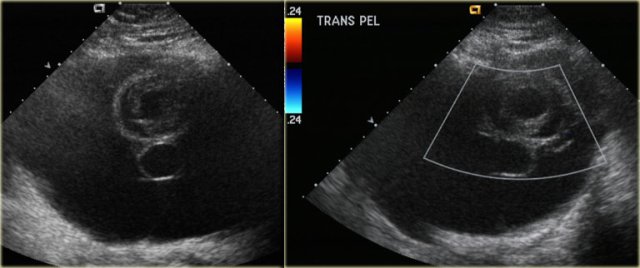

The US images are of a young pregnant woman, who had multiple ovarian cysts. The other ovary is not shown but showed a similar appearance.

The features needed to make the diagnosis of ovarian hyperstimulation syndrome are in the clinical history - a young pregnant woman - and in the last image of the uterus, which shows an invasive uterine mass, consistent with invasive molar pregnancy.